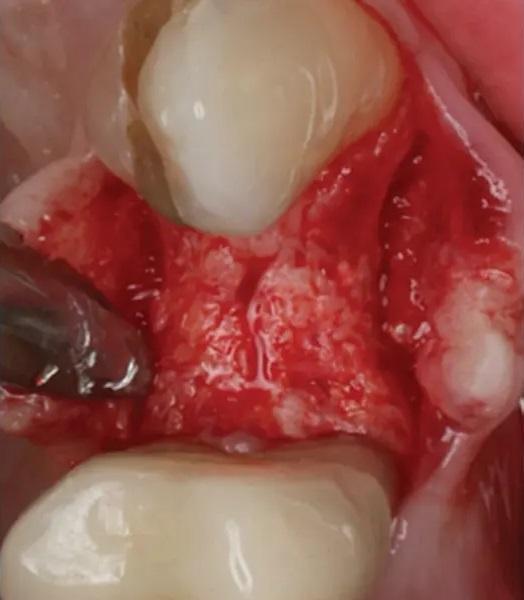

Существующая реставрация (№ 2.4) была разделена для получения доступа к фуркации. Оба корня (щечный и небный) были удалены с использованием периотомов, элеваторов и щипцов. Лунка была очищена от грануляционной ткани, которая отправлена на гистопатологический анализ. ПА рентгеновский снимок подтвердил полное удаление корней. Процедура САГ была выполнена с использованием упомянутого выше резорбируемого ксеногенно-аллопластического биоматериала (OsteoGen Plug), который был адаптирован в лунку (Фото 6). ПА рентгеновский снимок подтвердил правильное размещение биоматериала. Участок был ушит швом из политетрафторэтилена (ПТФЭ) (Фото 7 – Фото 10). Пациенту были даны инструкции по гигиене полости рта и послеоперационному уходу.

Фото 6. Пробка из ксеногенно-аллопластического биоматериала была подточена для оптимальной адаптации к лунке.

Фото 7. Удаление первого премоляра верхней челюсти слева. Свежая лунка демонстрирует сохраненный контур мягких тканей.

Фото 8. Вестибулярный лоскут слегка отслоен, видны хороший уровень васкуляризации и немедленное образование кровяного сгустка в лунке.